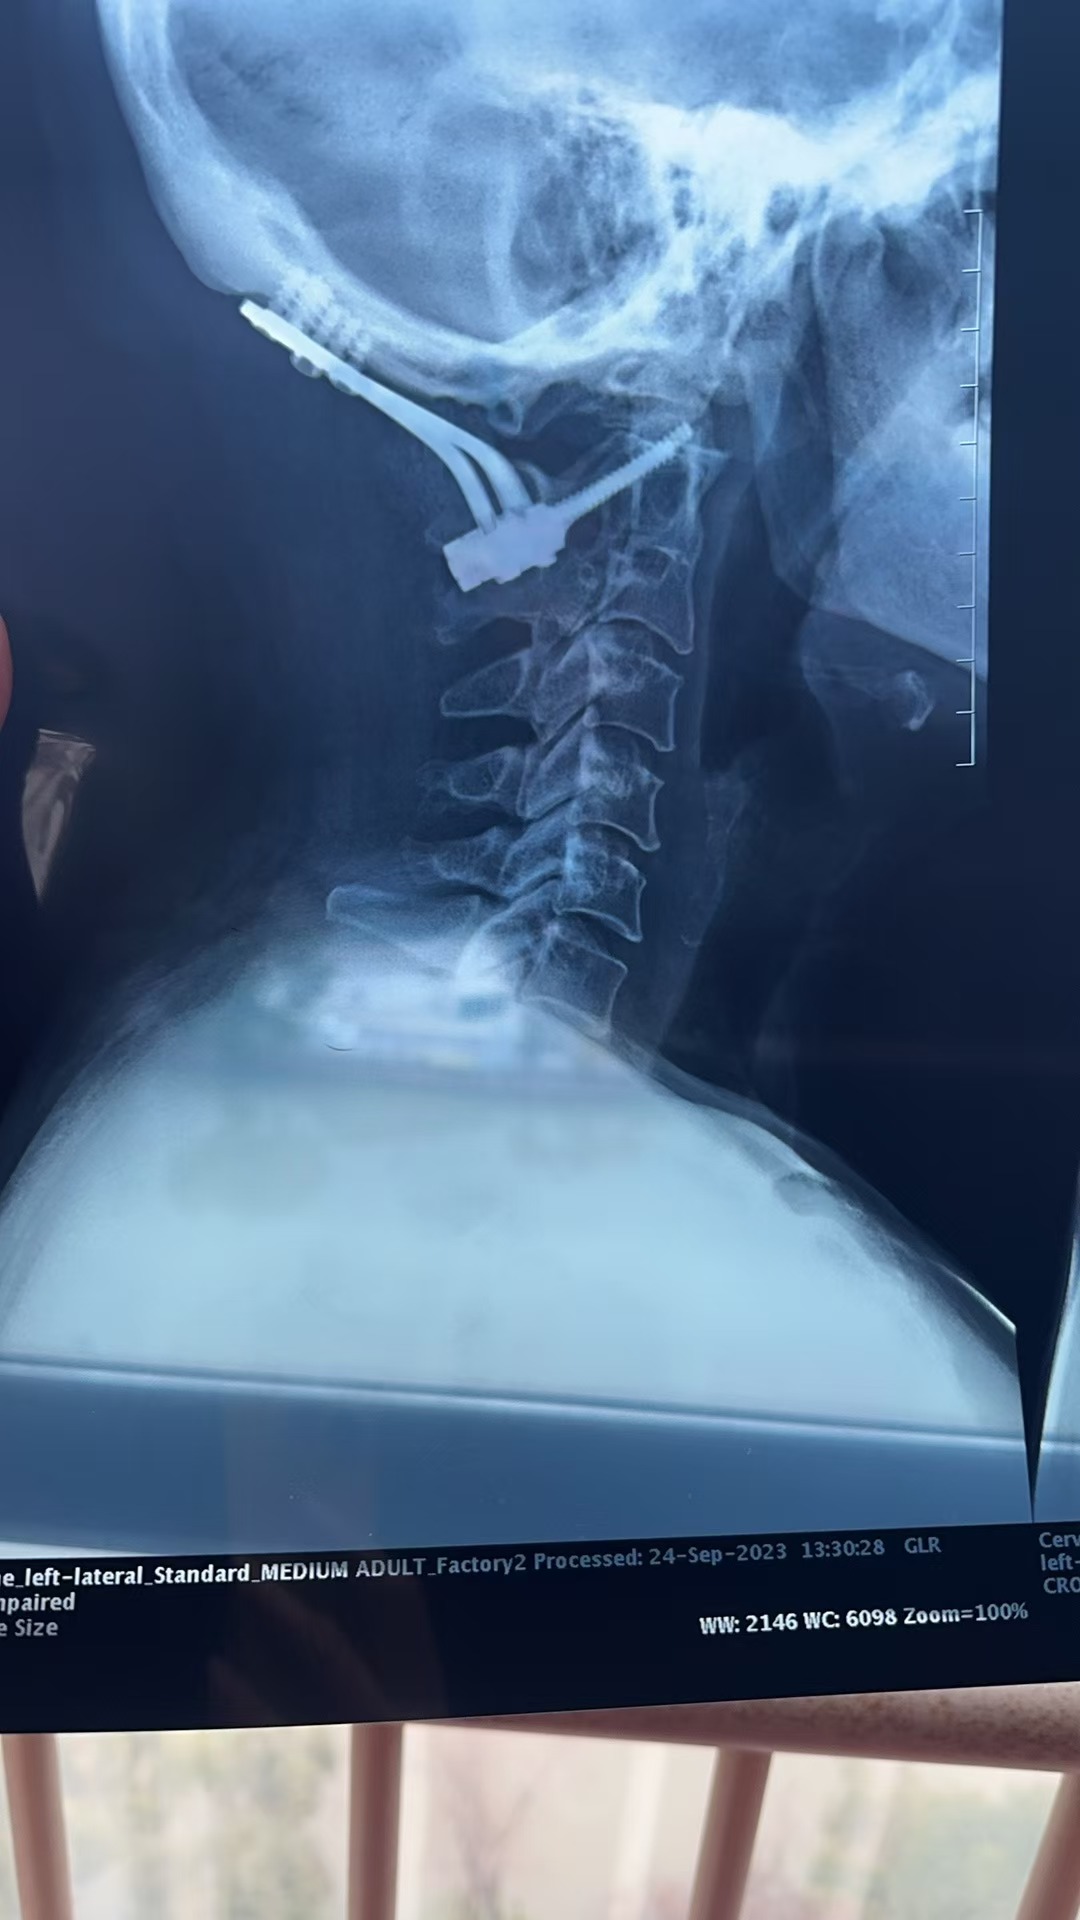

• 诊断:寰枢椎脱位,颅底凹陷

• 日期:2023.09

• 医院:北三医院

• 主刀:王超

• 术后影像: